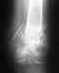

последствия оскольчатого перелома пяточной кости.

Вечером 2008г. выпала со 2-го этажа, скорая только на следующий день отвезла в больницу. В больнице наложили гипс под углом 90градусов и отправили домой...

Лечащий врач мне операцию не назначил, по прошествии 3-х месяцев сняля гипс: стопа стала кривой на втнутреннюю сторону. Три года я мучилась: нога болела, заметно хромала, появилось плоскостопие, прогулки заканчивались дикими болями и отеками. Посетила множество хирургов, травматологов ни один не дал направления на операцию. В январе этого года посетила еще одного травматолога, попросила что бы сделалали операцию, а он мне заявил что уже поздно мы ничего сделать не сможем, если хочешь обращайся в платную поликлинику. За деньги мне обьяснили что операция была необходима сразу и согласились ее провести. Мне вставили трансплантант взятый из моей тазовой кости, фиксировали винтами, пяточной пластиной.Врезультате стопа стала еще кривее, так же мне больно ходить, пожалуй изменение заключается только в добавлении шрамов.